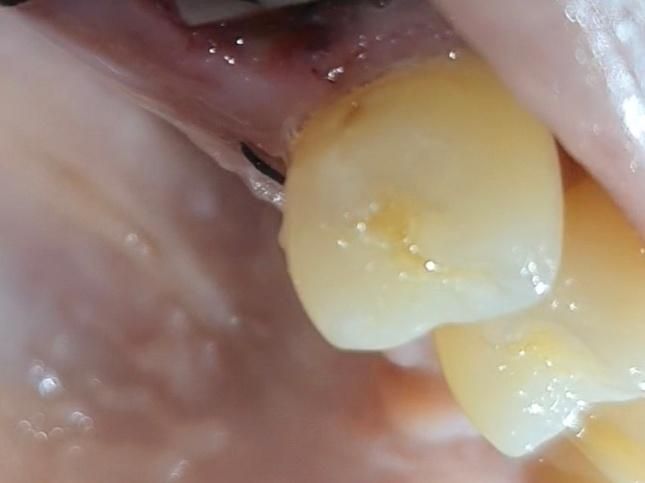

발치한 치아 앞뒤 치아 옆면 충치? 착색?

앞뒤로 치아 옆이 긁힘? 살짝 패여있는데

충치인지 착색인건지...

• 1번 째 사진

사진에 보이는건 치아 옆면에 충치가 잇는거 같습니다. 엑스레이 촬영후 치료를 하시는게 좋을것같습니다.

스케일링하면서 주위 착색 제거하고 착색제거후 남은 충치는 간단한 충치치료를 해주시면 좋을거 같습니다. 충치 치료 완료후 연마를 시행하게 되면 치면이 더 부드러워져서 음식물이 달라붙는 현상도 많이 감소할거같습니다. 근처 치과에서 상담후 치료 진행하시면 될거 같습니다.

사진으로만 봤을 경우에는 치아 표면에 작은 충치가 생긴것으로 보입니다. 이런 충치는 간단하게 치료를 할수도 있습니다.

둘 다 충치로 보여집니다. 보통 치아를 뽑고 나면 앞 뒤 치아에 발견하지 못한 충치가 많이 발견됩니다. 현재 상태에서는 특별히 접근이 어렵지 않으므로 간단히 레진 등으로 수복할 수 있는 정도이므로 임플란트나 다른 치료를 하기 전에 먼저 간단히 치료를 하는 것을 권해드립니다.

사진으로 봐서는 좀 애매하고 탐침 등의 기구로 긁어봤을때 긁히면 떼워주면 좋을 것 같습니다 깊은 충치는 아닌 것 같습니다